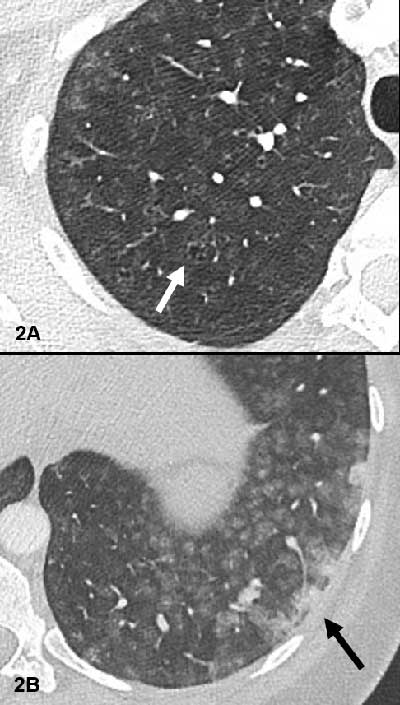

Figure 2

Small centrilobular apical emphysema (white arrow Figure 2A) and confluent condensed areas in the basal segments of the lower lobes (black arrow Figure 2B).

A CT angiogram revealed no evidence of pulmonary embolism. However, diffuse groundglass centrilobular nodules without tree-in-bud pattern were observed (Figure 1), in association with small centrilobular apical emphysema (white arrow Figure 2A) and confluent condensed areas in the basal segments of the lower lobes (black arrow Figure 2B). The first diagnostic hypothesis was hypersensitivity pneumonitis, though there was no air-trapping on the CT. The etiological investigation failed to find any causative agent for this pathology.

CT findings in a patient with talcosis include diffuse centrilobular nodules, ground-glass opacities, confluent masses with internal foci of high attenuation that are consistent with talc deposition, and emphysema. This centrilobular distribution of the micronodules is suggestive of bronchiolar or vascular involvement. In talcosis associated with use of intravenous drugs, the lung apices and costophrenic sulci are generally spared. Furthermore, if emphysema is present, it is typically centrilobular or apical in talcosis by inhalation while it is panlobular with a basal predominance in the intravenous form [1]. The CT pattern in our case orientates towards an inhalative exposure.